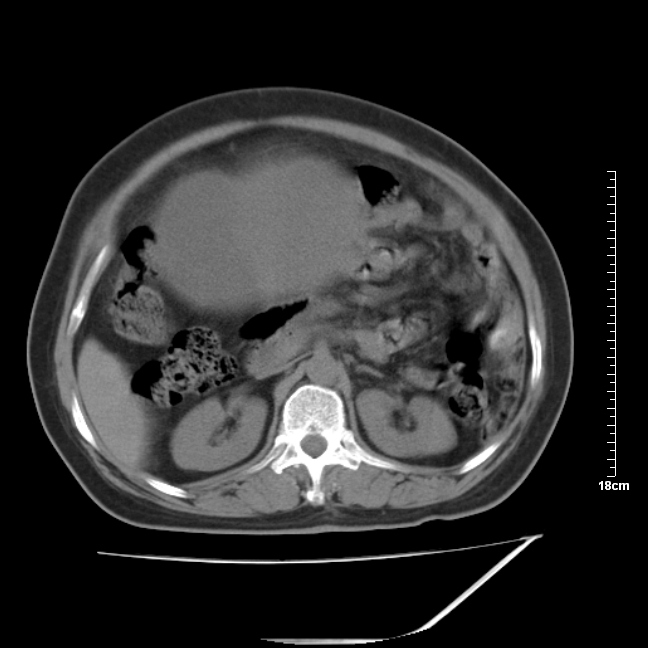

以下是引用jinning在2007-5-17 11:18:00的发言:[br]考虑右侧卵巢囊腺瘤合并少量出血可能性大